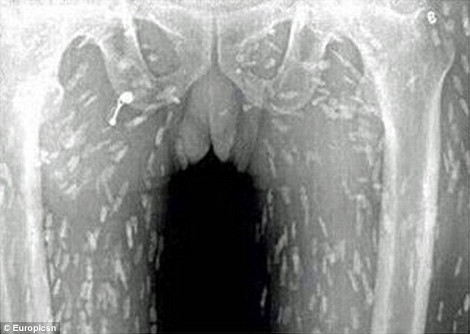

Σύμφωνα με τη Daily Mail, ένας άνδρας επισκέφθηκε τον γιατρό του στην επαρχία Guangdong της ανατολικής Κίνας, έπειτα από στομαχικούς πόνους κι έντονη φαγούρα. Προς μεγάλη του έκπληξη ανακάλυψε ότι στις ακτινογραφίες στις οποίες είχε υποβληθεί, διακρίνονταν εκατοντάδες σκουλήκια να «αλωνίζουν» στο έντερό του και σε άλλα ζωτικά όργανα. Αιτία, σύμφωνα με τους γιατρούς, δεν είναι άλλη από την κατανάλωση χαλασμένου ωμού ψαριού, δηλαδή σούσι. Ο ασθενής εισήχθη στο νοσοκομείο για θεραπεία.